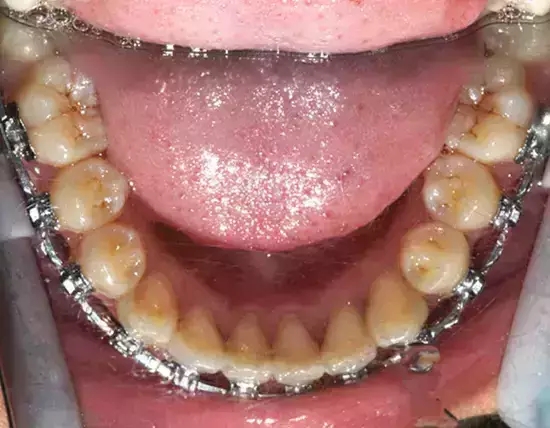

Damon 病例分享:安氏 II 類(lèi)二分類(lèi)露齦笑的矯治(董一磊)

治療前后對(duì)比